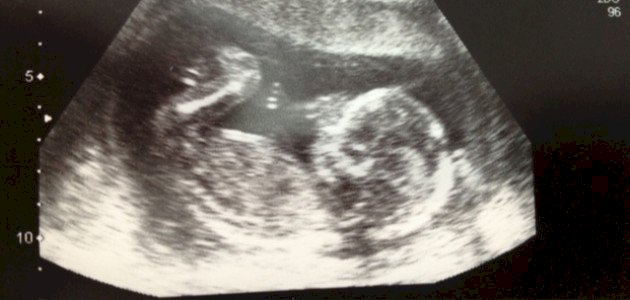

يمتد الشهر الرابع من بداية الأسبوع الرابع عشر إلى نهاية الأسبوع السابع عشر من الحمل،[١] ونبين فيما يأتي كيفية تغير شكل الجنين خلال هذه الأسابيع بشيءٍ من التفصيل:

الأسبوع الرابع عشر

تطرأ العديد من التغيرات على الجنين خلال الأسبوع الرابع عشر من الحمل، وفيما يأتي بيان أبرز هذه التغييرات:

- يكون حجم الجنين في هذا الأسبوع من الحمل بحجم حبة الليمون؛ إذ يصل طوله إلى ما يقارب 9 سنتيمترًا، ويبلغ وزنه 43 غرام تقريبًا.[٢]

- تكون أعضاء الجنين قد بدأت بالتمايز عند الوصول للأسبوع الرابع عشر من الحمل؛ لذلك عند فحص الجنين يظهر كل من ساعديه، ومعصميه، ويديه، بالإضافة إلى أصابعه بشكلٍ جيد، أما العينين فتظهران على شكل مناطق داكنة خلف الجفون المغلقة، إذ تنتقل العينان إلى جانبي الرأس من الداخل.[٣]

- يزداد طول كل من الذراعين والساقين خلال هذه المرحلة، ويصبح الجنين قادرًا على تحريكهما بحرية، إلاّ أنّ حجم الرأس يكون كبيرًا مقارنةً بحجم الجنين، وتكون جبهته منتفخة قليلاً.[٤]

- تظهر عظام الأنف من جهة جسر الأنف فقط، وتبدأ عظام الفك العلوي والسفليّ بالظهور، بالإضافة إلى أنّ الحبل السري ينشأ من مركز البطن.[٥]